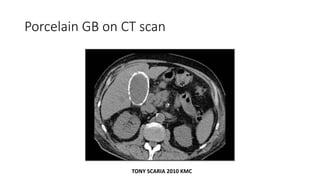

Porcelain GB can be seen on x ray 

indication for cholecystectomy

• As it is premalignant

Porcelain GB

Porcelain GB on CT scan